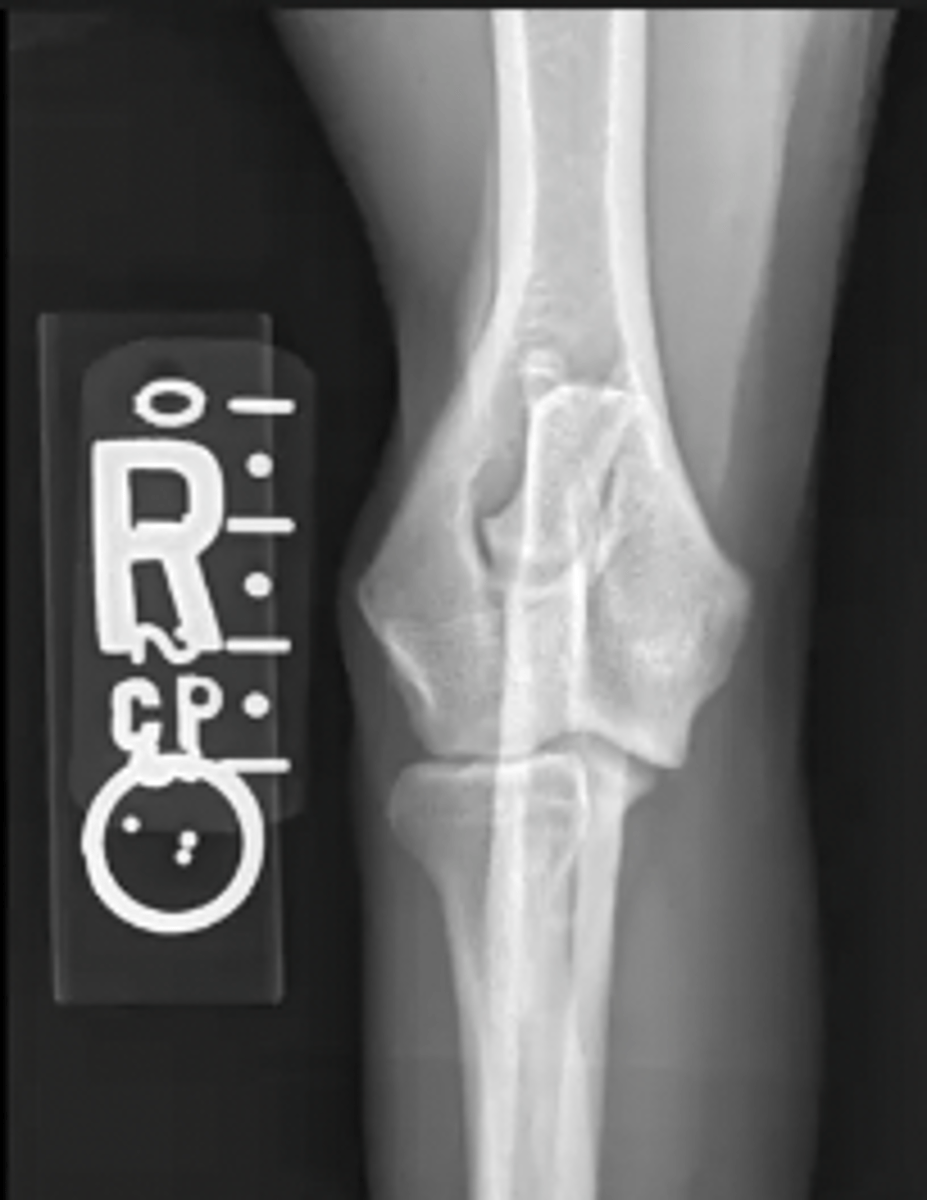

craniocaudal canine elbow

What is the view of this image?